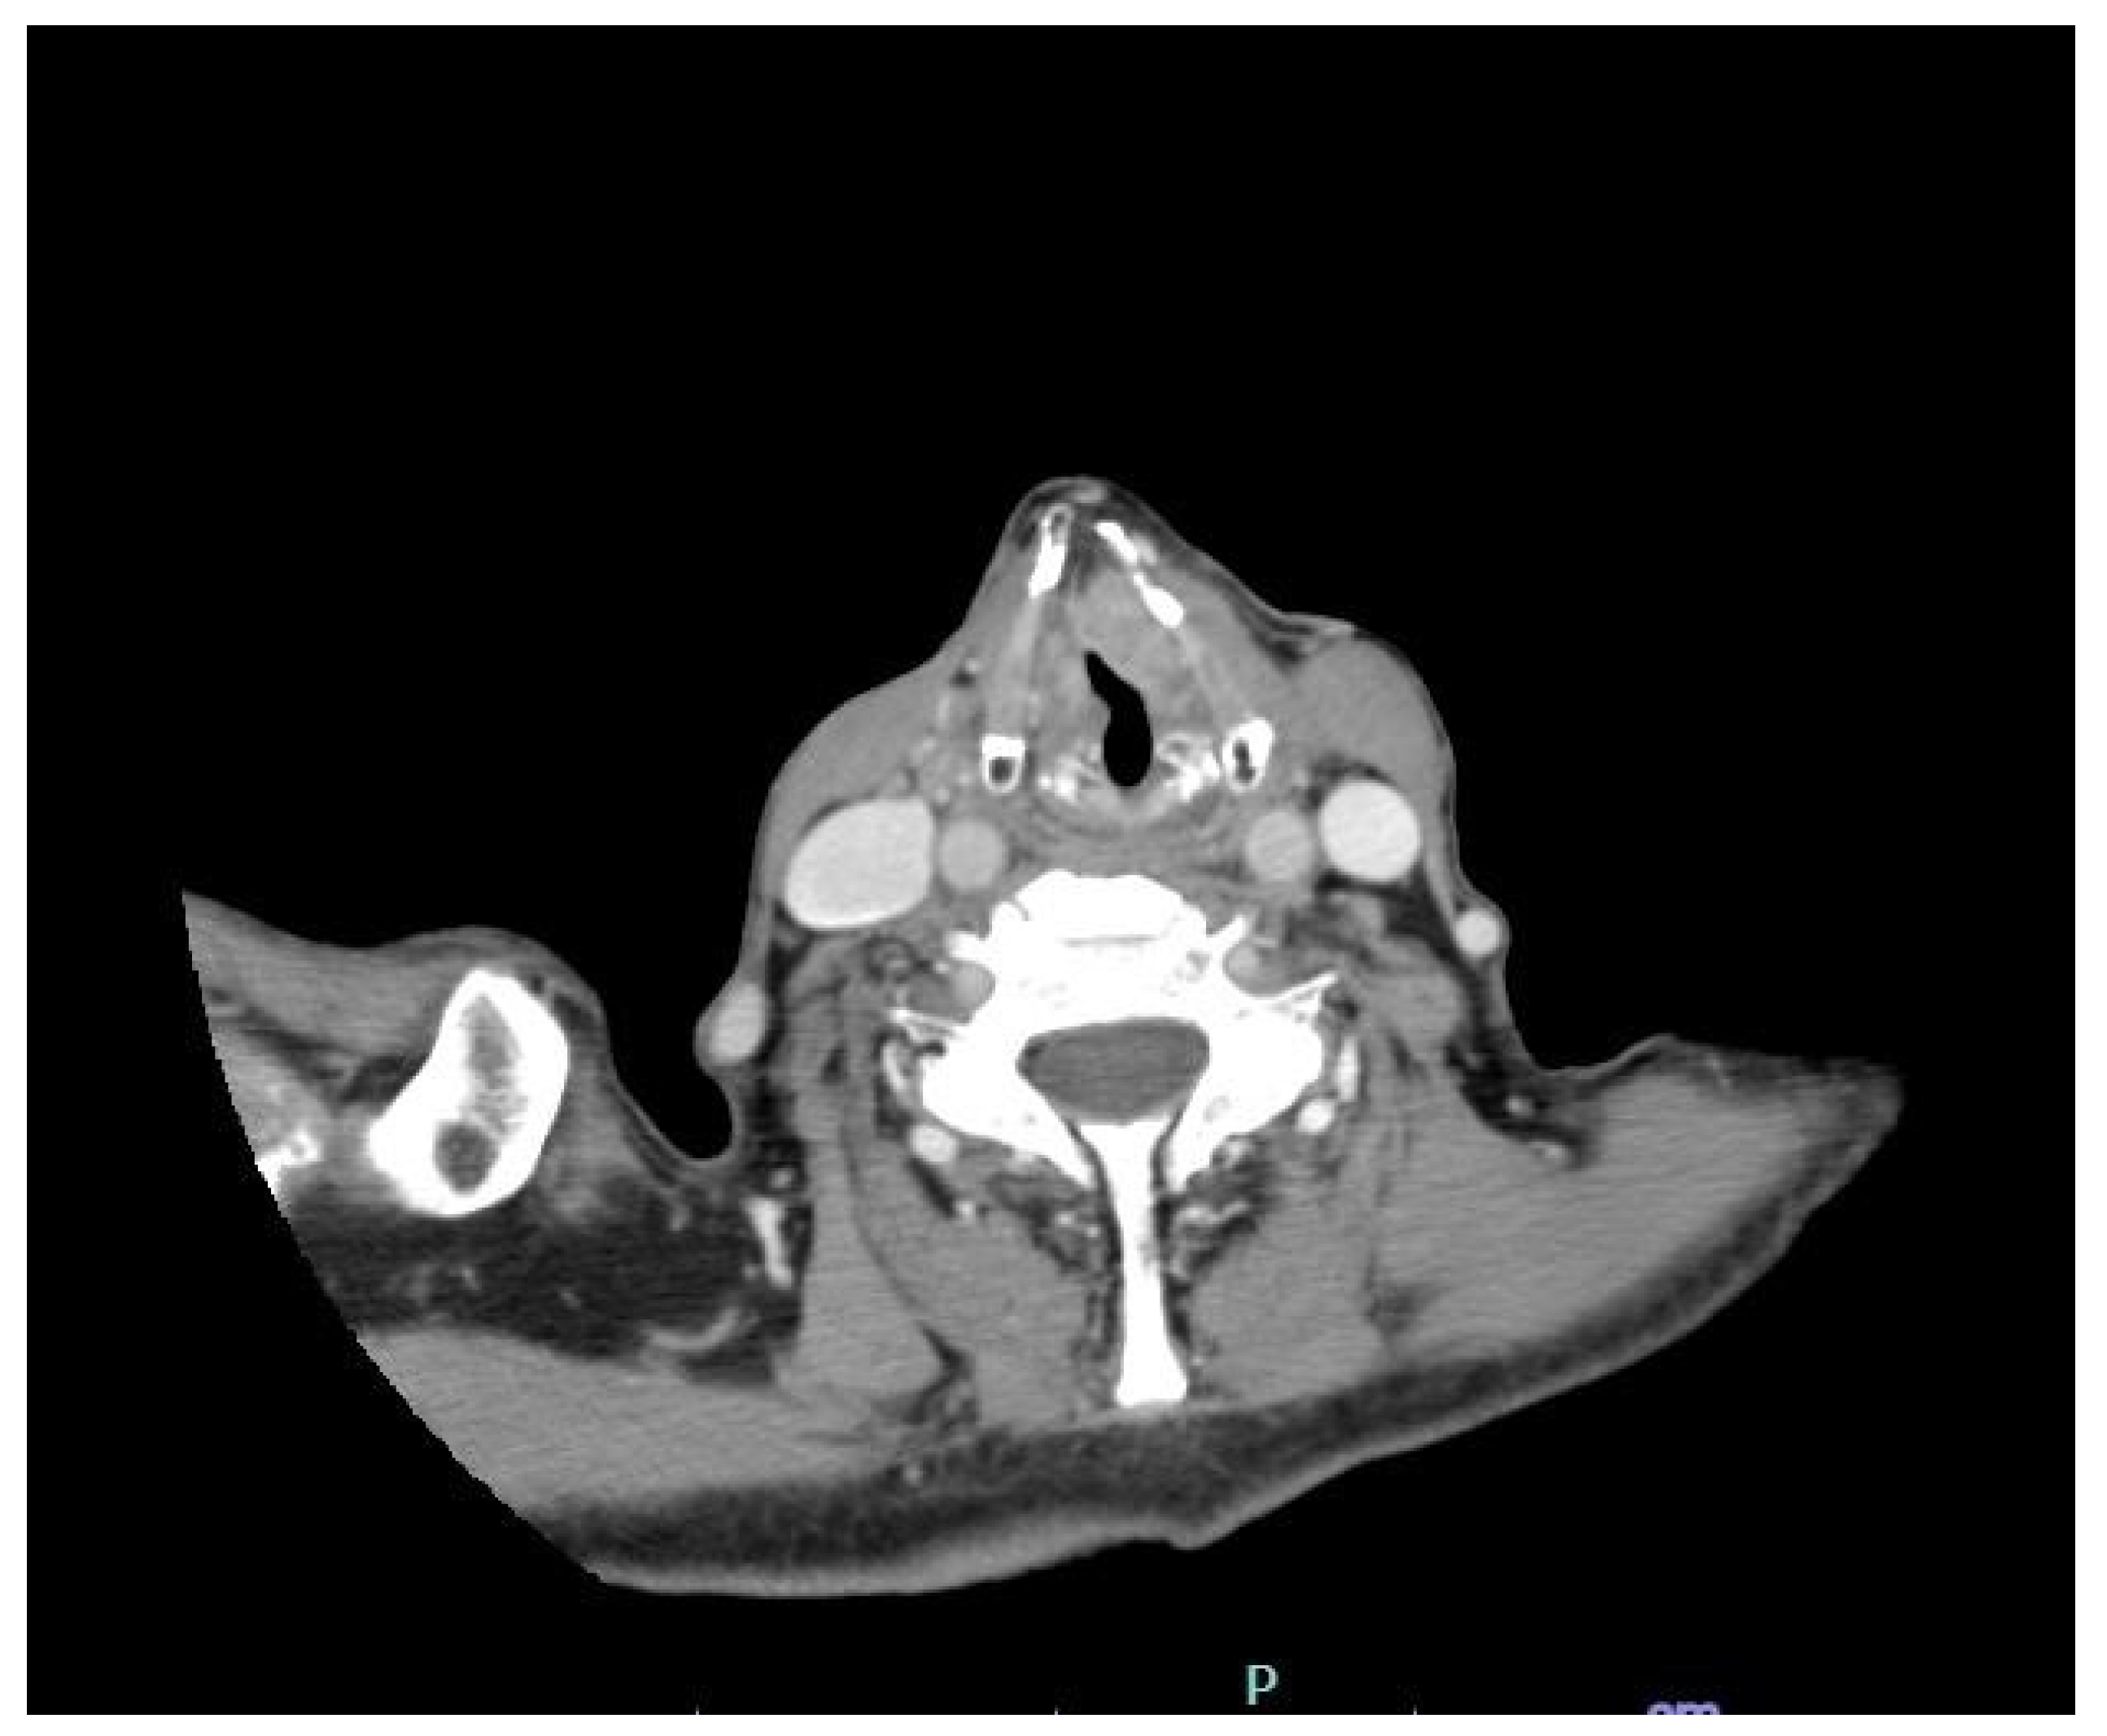

2. Case Presentation

| 2 | Radiological investigation |